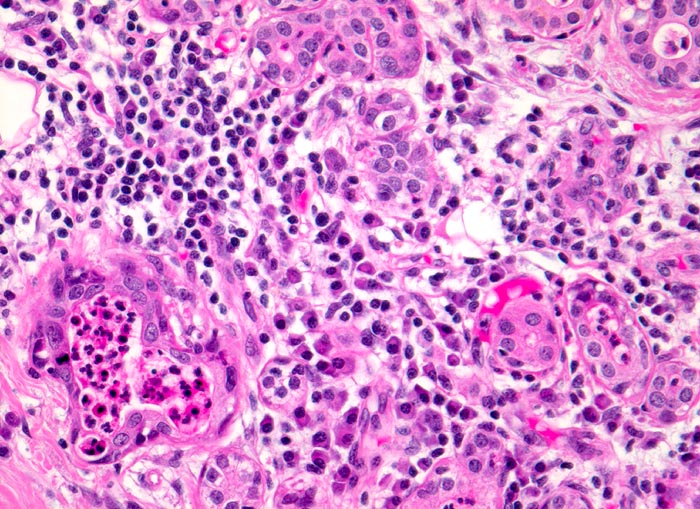

Akute Sialadenitis

Akute bakterielle Sialadenitiden werden oft verursacht durch eine Gangobstruktion (z.B. Steine), können aber auch bei schlechter Mundhygiene oder bei Immunsupression vorkommen. Die Feinnadelpunktion kann durch eine Druckverminderung zu einer Schmerzreduktion führen. Das Punktat gleicht einem Abszess mit neutrophilen Granulozyten, Fibrin und Nekrosen. Gelegentlich sind Erreger nachweisbar. Zu einem späteren Zeitpunkt kommen Lymphozyten, Plasmazellen, Makrophagen, Granulationsgewebe und Epithelien mit regenerativen Veränderung/Atypien zur Darstellung.